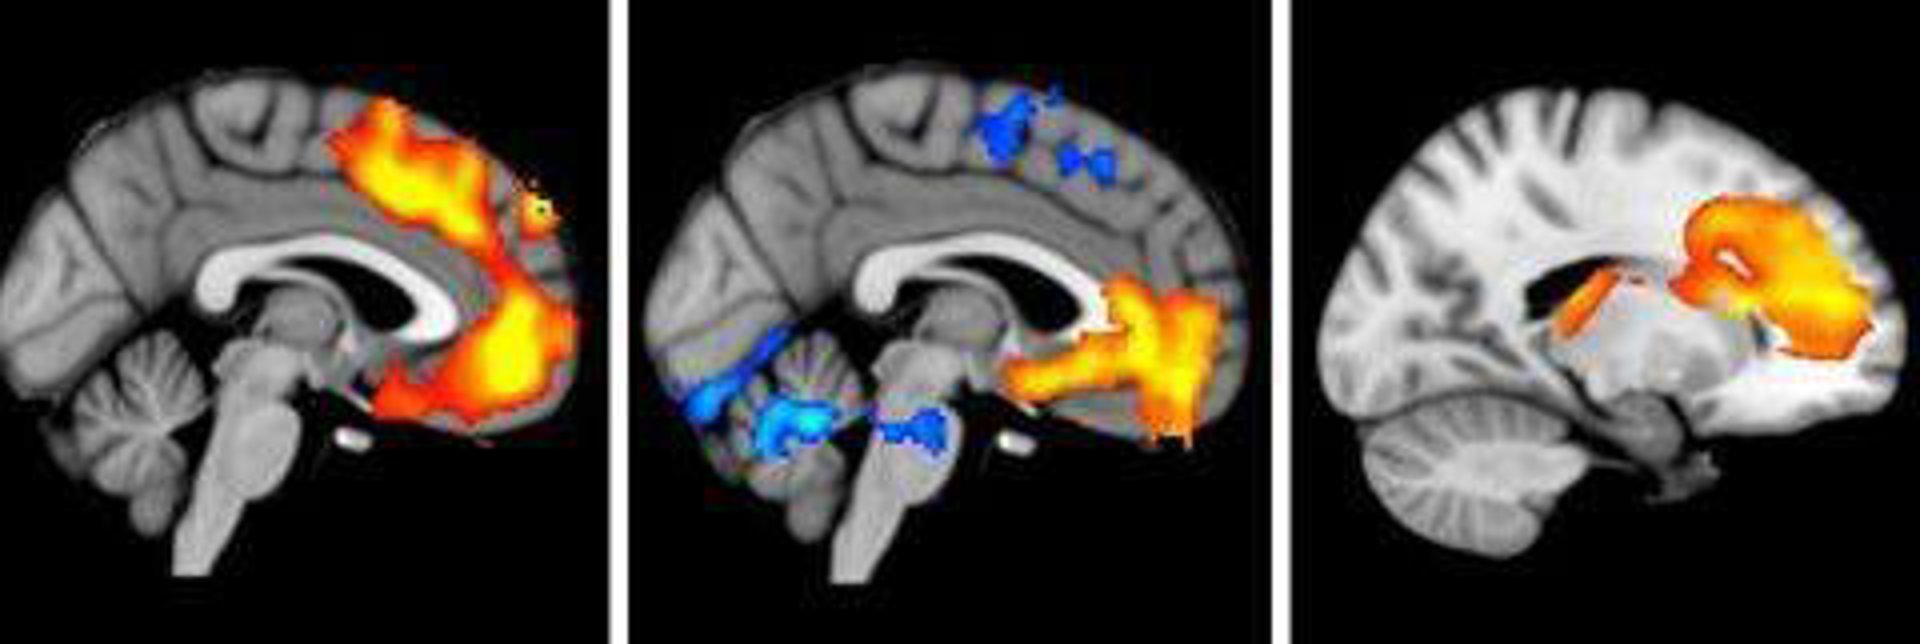

Estos investigadores, liderados por la doctora Edith Pomarol-Clotet, examinaron y compararon el cerebro de 32 pacientes con esquizofrenia con el de otras tantas personas sanas mediante tres técnicas de resonancia diferentes con las que medían el volumen de materia gris del cerebro, las conexiones de la sustancia blanca subyacente y el patrón de actividad en diferentes partes del cerebro mientras los sujetos realizan un test de cognición.

De este modo, comprobaron que con las tres técnicas han identificado la misma región cerebral --la citada corteza frontal media-- como anormal en los pacientes con esquizofrenia, lo que tiene "especial importancia porque no existe ningún trabajo anterior sobre esta enfermedad que haya encontrado anomalías cerebrales estructurales y funcionales localizadas en la misma parte del cerebro.

Esta área cerebral está incluida en los lóbulos frontales situados en la parte anterior del cerebro y ya implicados en la patofisiología de la esquizofrenia por muchos estudios. La corteza frontal media forma parte de una red de regiones cerebrales, denominada 'Default Mode Network' (o red neuronal por defecto) y, aunque ya había sido descubierta recientemente, parece tener un "papel crucial en la creación y elaboración de los pensamientos que todos tenemos cuando no estamos ocupados en ninguna tarea mental concreta".